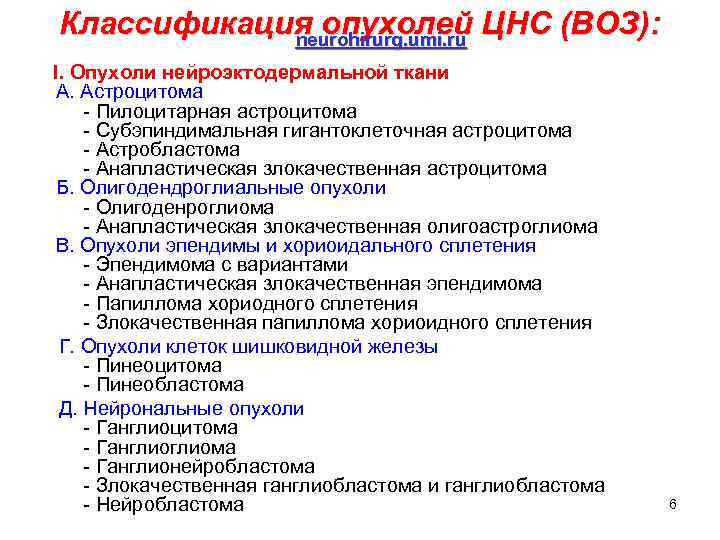

Классификация опухолей ЦНС (ВОЗ): neurohirurg. umi. ru I. Опухоли нейроэктодермальной ткани А. Астроцитома - Пилоцитарная астроцитома - Субэпиндимальная гигантоклеточная астроцитома - Астробластома - Анапластическая злокачественная астроцитома Б. Олигодендроглиальные опухоли - Олигоденроглиома - Анапластическая злокачественная олигоастроглиома В. Опухоли эпендимы и хориоидального сплетения - Эпендимома с вариантами - Анапластическая злокачественная эпендимома - Папиллома хориодного сплетения - Злокачественная папиллома хориоидного сплетения Г. Опухоли клеток шишковидной железы - Пинеоцитома - Пинеобластома Д. Нейрональные опухоли - Ганглиоцитома - Ганглиома - Ганглионейробластома - Злокачественная ганглиобластома и ганглиобластома - Нейробластома 6